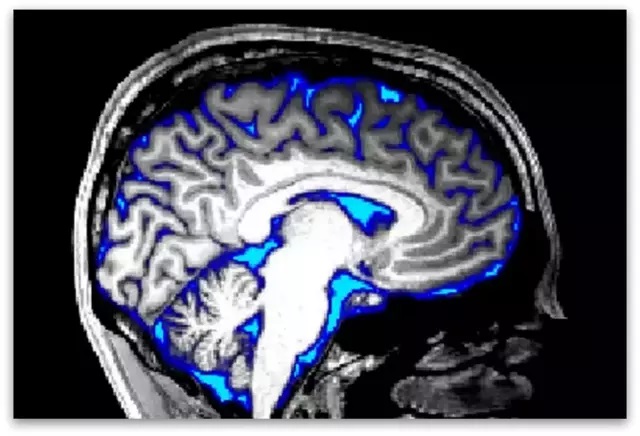

Lewis и нејзиниот тим користеле нова техника за скенирање на мозокот, користејќи постојни машини за снимање со магнетна резонанца, кои ја истакнуваат секоја течност што штотуку влегла во четвртата комора на мозокот, шуплината на основата на главата. Течноста што влегува во оваа комора тече низ гореспоменатиот glymphatic system.

Кога беше прикажан моделот, тоа предизвика зголемување на протокот на крвта во визуелните центри на мозокот, како што се очекуваше. Кога екранот се стемни, протокот на крвта се намалуваше, но протокот на течност во мозокот се зголеми.